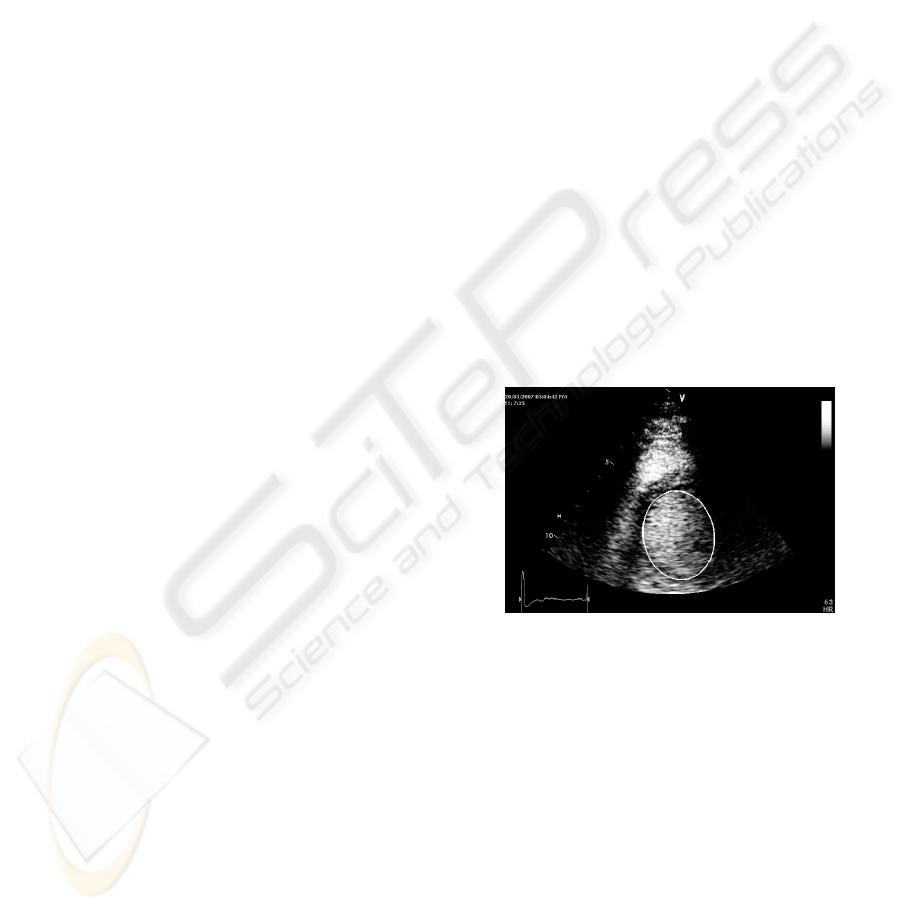

ENDOCARDIAL SEGMENTATION IN CONTRAST ECHOCARDIOGRAPHY VIDEO WITH DENSITY BASED

SPATIO-TEMPORAL CLUSTERING